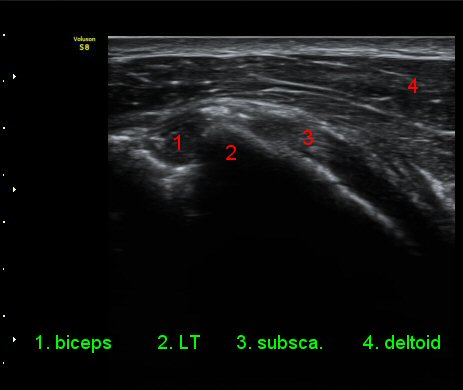

ÃÊÀ½ÆÄ °Ë»ç

ŽÃÊÀÚ¸¦ ¾à°£ ´Ù¸®ÂÊ, ³»ÃøÀ¸·Î À̵¿ÇÏ´Ï °ß°©ÇÏ±Ù°Ç Ç¥Ãþ¿¡ ¸¹Àº ¾çÀÇ ¼ö¾×Àú·ù°¡ °üÂûµÈ´Ù(»çÁø 3).

ÆÈÀ» ¿ÜȸÀüÇÏ´Ï °ß°©ÇÏ±Ù°Ç Ç¥ÃþÀÇ ¼ö¾×Àú·ù°¡ ´õ¿í È®½ÇÇÏ°Ô °üÂûµµ´Ï´Ù(»çÁø 4).